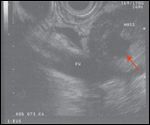

The patient then came to our institution for further management. An endoscopic ultrasound (EUS) visualized a 3.5 × 2.2 cm irregular cystic lobulated mass in the pancreatic head, with clear involvement of the portal vein at the confluence with the superior mesenteric vein (SMV), causing limited occlusion (Figure 3). Fine-needle aspiration (FNA) was performed during EUS and revealed well differentiated pancreatic adenocarcinoma with papillary features. The patient experienced a recrudescence of his presenting symptoms and required repeat ERCP to replace an occluded biliary stent.

FIGURE 3

SMV/PV Involvement